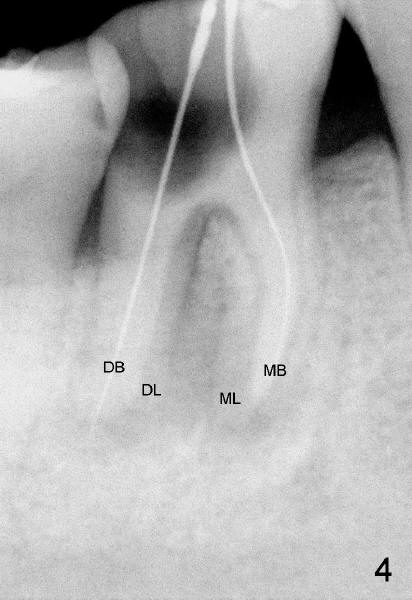

A healthy 43-year-old lady requests saving the tooth #30 with large DO caries and perioapical radiolucency (Fig.1). The tooth appears to have mesial (M) and distal (D) roots. Different angulation PA (Fig.2) and Bitewing (Fig.3) show that there are totally 4 roots/canals, which is not noted by the operator before RCT or after initiation of RCT (Fig.4). The distal canal orifice is not in the center. The distolingual (DL) canal orifice is searched without success. MB, ML, and D canals are debrided with rotary file 30/.04 at working lengths (WL).